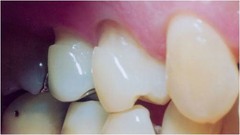

amelogenesis imperfecta on radiograph

Front

Back